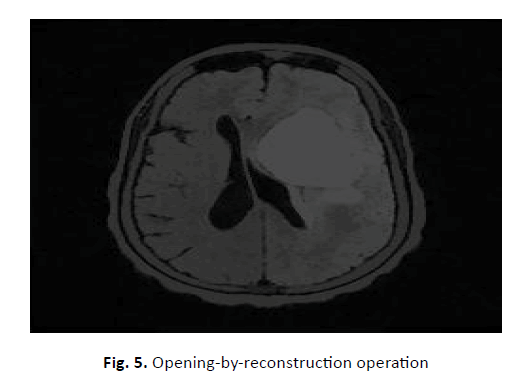

This experimental study was conducted to find an accurate brain tumour segmentation method using a parallel computing algorithm. For ten patients with T1 and T2 MRI data, a new potential field segmentation algorithm was used. In total, 200 MRI images were used in this was study. The manually defined fields compared segmented GTVs with the Q, DSC, and other measures. Figure 3 shows the original images before applying watershed segmentation. Figure 4 shows the application of the Sobel edge masks that were used for gradient magnitude computation. Masks, image filters, and a few simple arithmetic methods were used to measure the gradient magnitude. The gradient is high at the object's border, and those of the objects are (mostly) low inside. Figure 5 shows the results of the opening-by-reconstruction algorithm using the opening-close reconstruction filter.

Figure 5: Opening-by-reconstruction operation